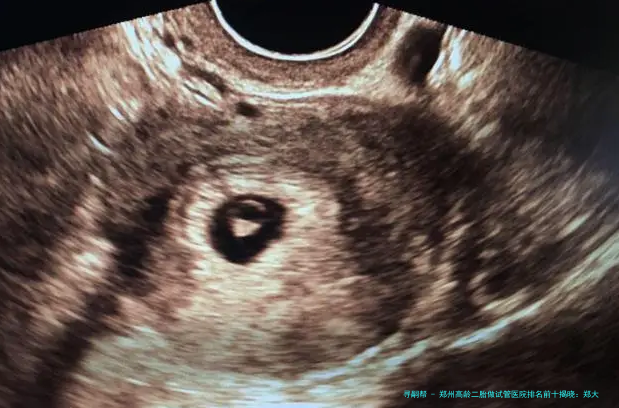

郑州高龄二胎做试管医院排名前十揭晓:郑大一附院、河南省生殖医院等领衔附试管婴儿名医与费用全解析

郑州高龄二胎做试管医院排行前十揭晓:郑大一附院、河南省生殖医院等领衔附试管婴儿名医与费用全解析